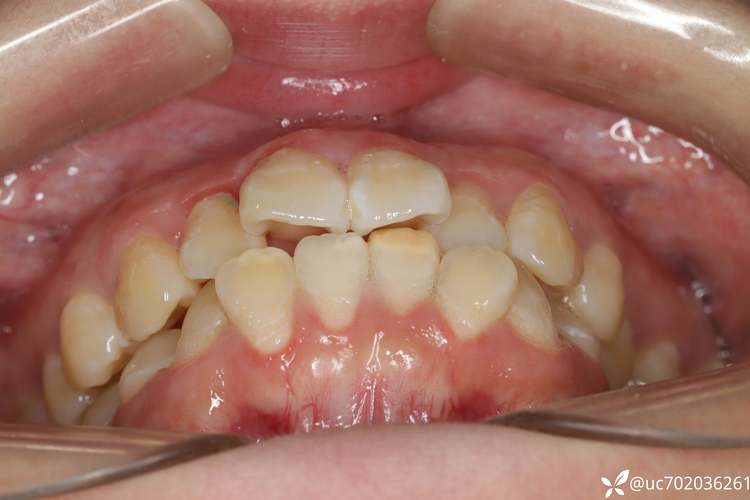

正畸治疗中,拔牙是解决牙齿拥挤、前突等问题的重要手段,而拔除3颗磨牙的情况相对少见,通常需要结合患者的具体口腔状况、牙齿排列、咬合关系及面部美学需求综合判断,与常见的拔除4颗前磨牙不同,拔磨牙涉及的功能和位置特殊性,需更谨慎的方案设计和术后管理。

正畸拔牙的核心目的是为牙齿移动创造空间,解决“骨量不足”或“牙量过多”的矛盾,磨牙位于牙弓末端,承担主要咀嚼功能,拔除3颗磨牙的决策往往基于以下复杂情况:

- 磨牙本身病变或位置异常:若第三磨牙(智齿)完全阻生、反复发炎,或第一/第二磨牙严重龋坏、根尖周炎无法保留,需优先拔除;若前磨牙区空间不足,可能需额外拔除1颗磨牙(如下颌第二磨牙)来协调牙量。

- 非对称性牙颌问题:单侧牙齿严重拥挤或前突,对侧磨牙早接触导致咬合紊乱,可能需要拔除患侧2颗磨牙(如第三磨牙+第一磨牙)和对侧1颗磨牙,通过非对称拔牙调整中线与咬合平衡。

- 特殊病例的代偿需求:如下颌发育过度、上颌发育不足的“Ⅲ类错颌”,为抑制下颌前伸、引导上颌前移,可能通过拔除下颌3颗磨牙(避免下牙弓过度后缩),配合上颌磨牙前移实现咬合稳定。